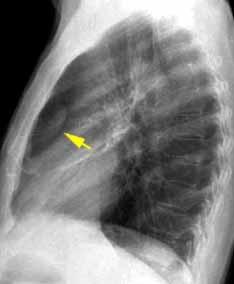

Derrame pleural 43-48% de pacientes con embolismo.

< 1/3 de hemitórax: 90%.(puede haber en lado opuesto).

Siempre exudados.

75% de los pacientes con TEP y derrame pleural tienen dolor pleurítico.

La disnea desproporcionada